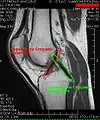

Intracapsular

The knee is stabilized by a pair of cruciate ligaments. These ligaments are both extrasynovial, intracapsular ligaments.[20] The anterior cruciate ligament (ACL) stretches from the lateral condyle of femur to the anterior intercondylar area.[13] The ACL prevents the tibia from being pushed too far anterior relative to the femur.[13] It is often torn during twisting or bending of the knee.[21] The posterior cruciate ligament (PCL) stretches from medial condyle of femur to the posterior intercondylar area. This ligament prevents posterior displacement of the tibia relative to the femur.[13] Injury to this ligament is uncommon but can occur as a direct result of forced trauma to the ligament.

MRI

Both anterior cruciate ligament (ACL) and posterior cruciate ligaments (PCL) are hypointense on both T1 and T2 weighted images of MRI. However, some high signal striations are often seen at the distal part of the ACL, making ACL higher intensity than PCL on MRI scans.[20]